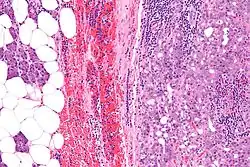

Micrograph of an acinic cell carcinoma (right of image) and acinar glands (parotid gland - left of image). H&E stain.

Histopathologic features

Basophilic, bland cells similar to acinar cells. Growth pattern: solid - acinar cells, microcytic - small cystic spaces mucinous or eosinophilic, papillary-cystic - large cystic lined by epithelium, follicular - similar to thyroid tissue.

These tumors, which resemble serous acinar cells, vary in their behavior from locally aggressive to blatantly malignant.